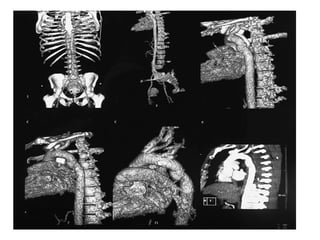

Computerised tomography scan

• has become the principal and most reliable

examination for major injury in thoracic

trauma.

• In blunt chest trauma the CT scan will allow

the definition of rib and vertebral fractures, as

haematomas,

• pneumothoraces and

pulmonary contusion

Computerised tomography scan •has become the principal and most reliable examination for major injury in thoracic trauma. • In blunt chest trauma the CT scan will allow the definition of rib and vertebral fractures, as haematomas, • pneumothoraces and pulmonary contusion